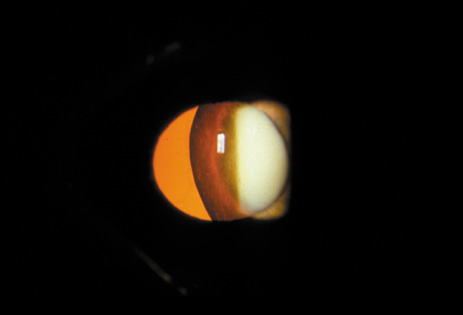

POSTERIOR SUBCAPSULAR CATARACT

The PSC is the least prevalent subtype in most population-based studies.18 These cataracts often occur in combination with nuclear or cortical cataracts in the later stages. They are easily noticed on retroillumination because they are usually located centrally, and may interfere with funduscopy (Fig. 12). In early stages, patients usually complain of subjective symptoms such as glare disability32 and difficulty focusing on near objects. This is because when the pupil constricts during accommodation, the light entering the eye becomes concentrated centrally, where the PSC is also located. This causes light scattering and interferes with the ability of the eye to focus an image on the macula. In addition, these opacities lie at or near the nodal point of the eye, further interfering with focusing of the image on the macula.

Fig. 12. PSC. Note the central location, which gives rise to severe glare disability.